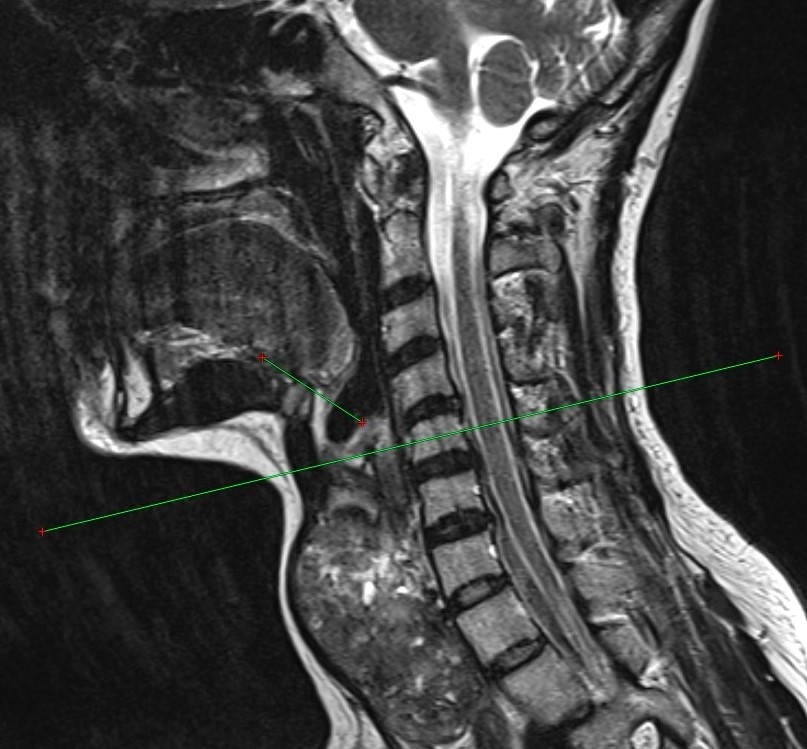

В Оренбургской области коллектив ученых разработал и получил патент на новый способ перевязки верхнего полюса щитовидной железы при ее увеличении. Авторами инновационной методики выступили доцент кафедры общей хирургии, кандидат медицинских наук Арина Жирнова и заведующий кафедрой оперативной хирургии и клинической анатомии имени Михайлова, профессор, доктор медицинских наук Сергей Лященко. Хирургическое лечение остается основным методом борьбы с заболеваниями щитовидной железы. Существующие техники перевязки верхних полюсов ориентированы на нормальный объем органа и не учитывают анатомические изменения при его увеличении. Новый метод позволяет точнее определять толщину и уровень расположения верхнего полюса увеличенной железы, а также снизить риск интра- и послеоперационных осложнений, таких как кровотечение и повреждение верхнего гортанного нерва. Методика проста в применении и может быть внедрена в любом стационаре, оснащенном компьютерным томографом, отметили в Центре медиакоммуник

Новый метод позволяет точнее определять толщину и уровень расположения верхнего полюса увеличенной железы, а также снизить риск интра- и послеоперационных осложнений, таких как кровотечение и повреждение верхнего гортанного нерва.

Методика проста в применении и может быть внедрена в любом стационаре, оснащенном компьютерным томографом, отметили в Центре медиакоммуникаций Оренбургского государственного медицинского университета.

Фото: Центр медиакоммуникаций Оренбургского государственного медицинского университета